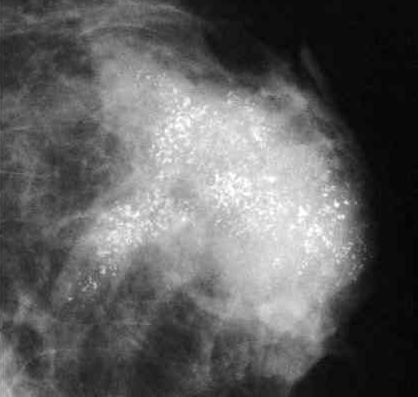

54岁的邓女士10余年前发现左乳肿物,伴有疼痛及乳头溢液,当时未予重视。9个月前在广州某医院就诊,经活检确诊为乳腺浸润性癌,三阴型。影像学检查提示肿瘤巨大、血供丰富,边界不清,肿瘤累及同侧胸壁并伴有多处淋巴结转移及双肺转移。

经历了化疗、免疫治疗、靶向治疗之后的肿瘤不但没有退缩,而且还在继续生长,以至于局部破溃出血,患者生活质量受到严重影响,甚至无法直立行走,来到中山一院就诊时,她胸前的巨大肿瘤已超过20cm,累及整个左胸前区皮肤。

▲患者胸前的巨大肿瘤已超过20cm

虽然多线姑息治疗效果欠佳,但患者还是希望能够通过手术来切除胸前这个巨大的肿块。此时的她除了肿瘤状况以外,还伴有严重的贫血表现,血红蛋白最低达49g/L,红细胞只有1.89 X 10^12/L,出现了低白蛋白血症等消耗性改变。

手术台上,肿瘤与术前评估一致,直径超过20cm,表面多处破溃,伴渗血及脓性分泌物。由于肿瘤与胸大肌、胸小肌紧密黏连,肿瘤内部感染和坏死,肿瘤周围血管增生,导致操作难度大,术中出血风险高。所幸,整个团队配合默契,将肿瘤连同胸大肌、部分胸小肌一起整体切除,最后利用负压引流装置封闭创面。